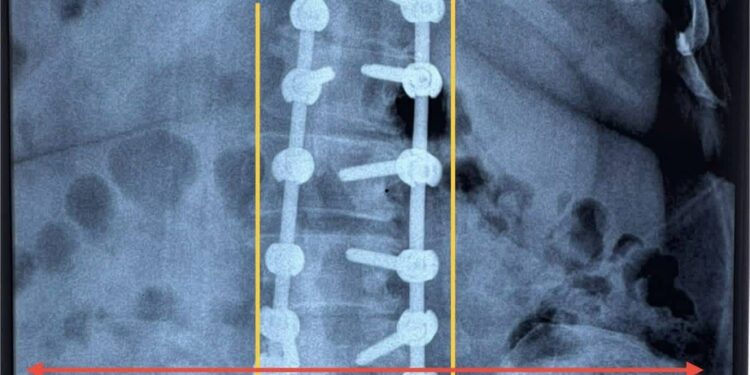

وبيّنت الإدارة أن الفريق الطبي قرر إجراء تداخل جراحي تضمن فتح الفقرات القطنية، وتحرير جذور الأعصاب، وتثبيت الفقرات باستخدام براغٍ وأعمدة من التيتانيوم، مع تعديل الاعوجاج القطني. وقد تكللت العملية بالنجاح، حيث اختفت آلام الظهر والأطراف السفلية لدى المريضة وتحسن الخدر بشكل ملحوظ.